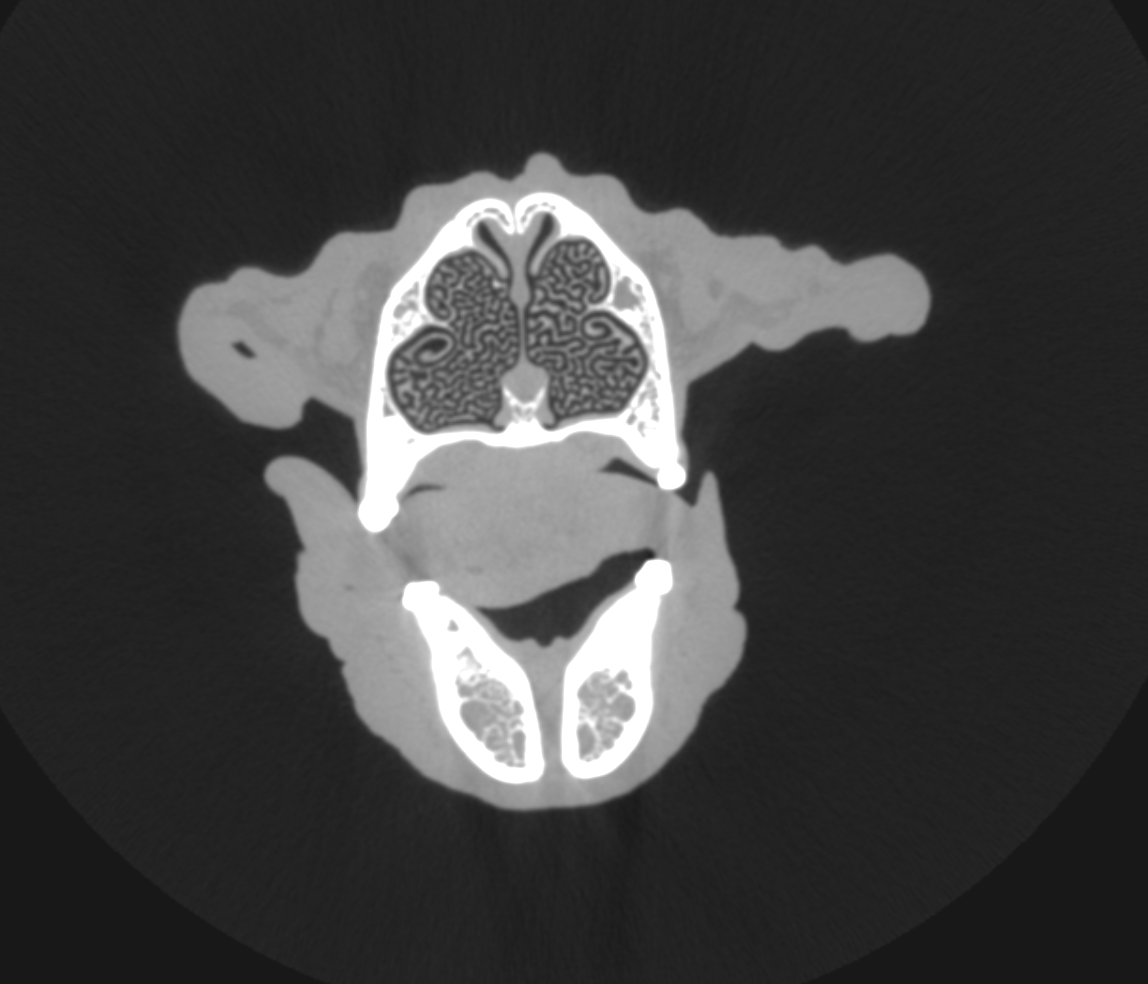

CT (Computed Tomography)

There are many indications for CT scan in animals - such as further evaluation of the nasal cavity, checking for ectopic ureters, finding abnormal vessels, etc.

Dog with normal nasal cavity and sinuses